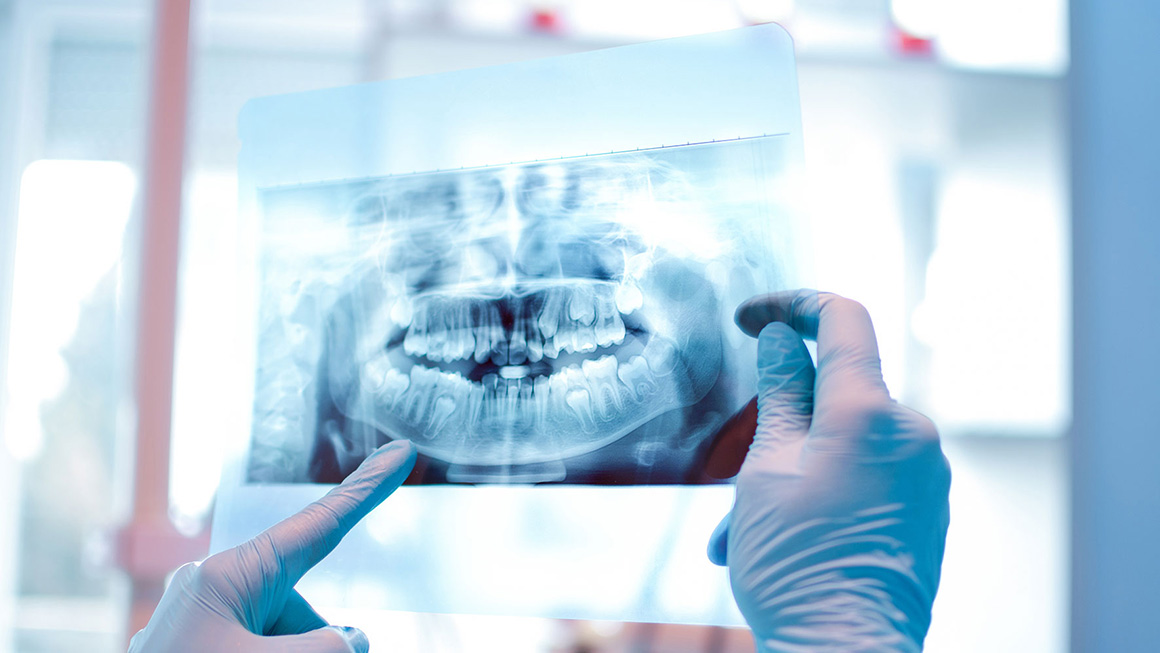

Kliniğimizde muayene ve tedavi olmak isteyen hastalarımızdan ilk önce anamnez formu alınmakta, extraoral ve intraoral klinik muayenesi yapıldıktan sonra diş hekimimizin gerekli görmesi halinde panoramic (2D) görüntüleme cihazı ile röntgen çekilmektedir.